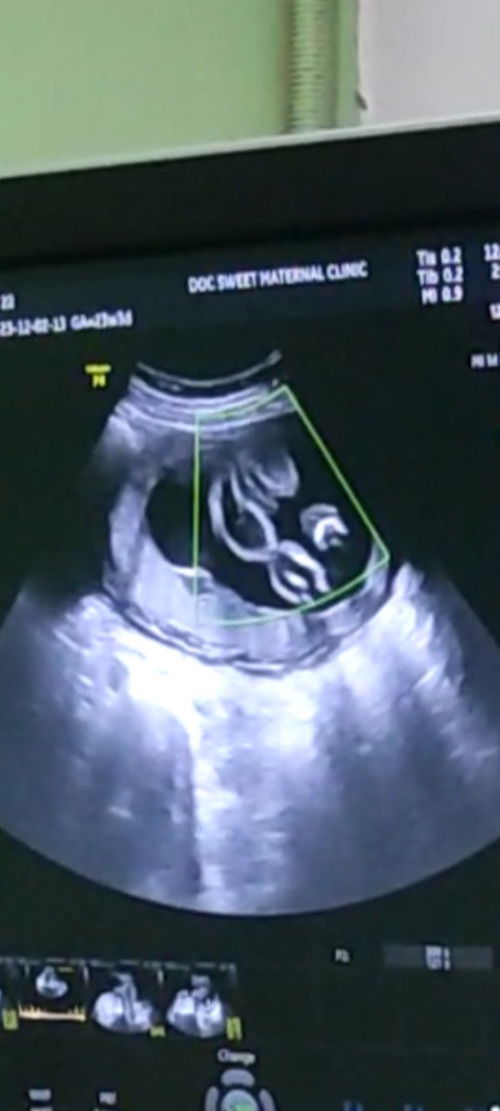

Pwede ba mabuntis agad after manganak.

Nag sex kasi kami ng asawa ko after 4 weeks full recovery nako and di sya nakapag condom di nya din pinuputok sa loob may tendency pa din bang mabuntis ket d pinuputok sa loob, ask ko lang nakakatakot kasi. Di maiwasan kasi ung asawa ko apaka kulet. Sana may makasagot salamaaat #AssianParent #respect_post